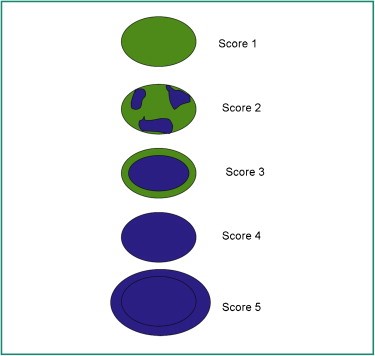

To determine the elasticity of changes, the Tskuba score was used with a rate from 1 to 5 (13, 14) (Figure 2).

Figure 2. The risk of malignancy increases from 1 to 5.

Tskuba score

Score 1: if the lesion is homogeneously elastic, completely green,

Score 2: if the larger lesion is deformable green, and only small parts of the areas are not deformed and are blue,

Score 3: deformable on the periphery of the lesion, and the center is rigid, blue,

Score 4: non-deformable blue lesion,

Score 5: lesion and adjacent tissues are stiff and blue.

According to Tsukuba score, almost all categories 1-3 are benign, and categories 4 and5 are malignant.